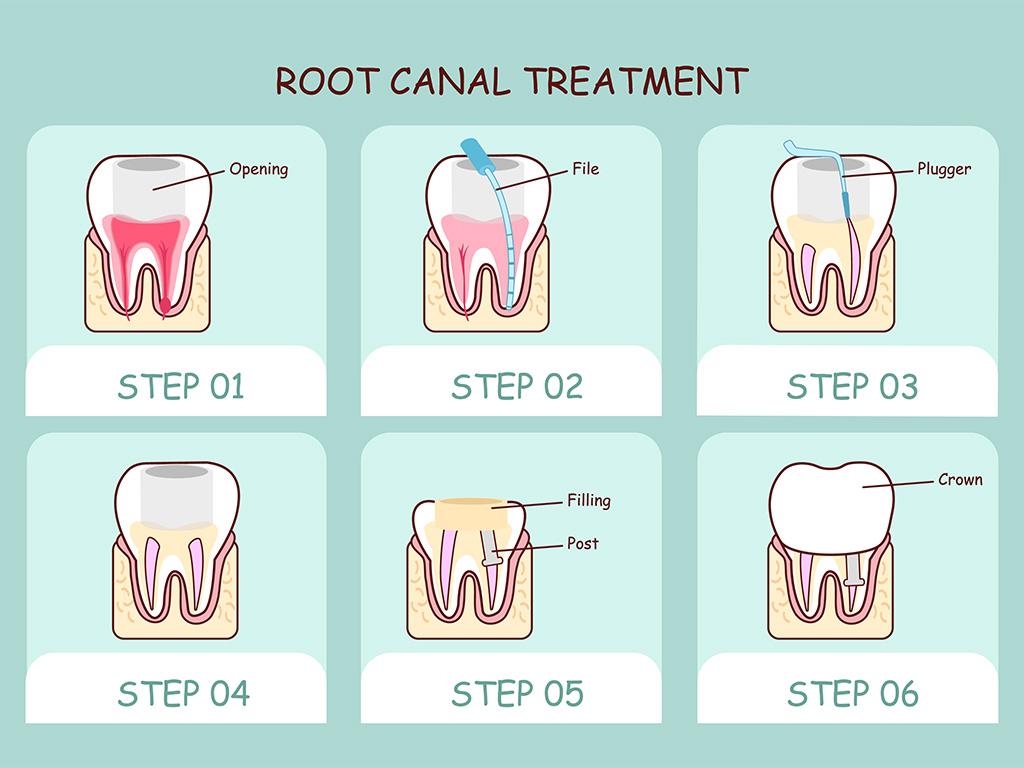

The Value of Root Canal Therapy

How to Know You Need Root Canal Therapy

Endodontics or Root Canal Therapy

Root Canal Therapy Myths

Root Canal Therapy: Do's and Don'ts